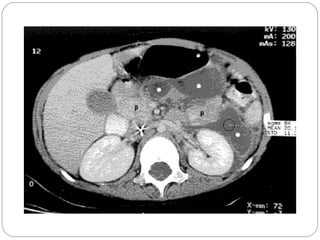

• Tomografía axial computadorizada con contraste:

Puede apreciarse la viabilidad del páncreas en las

zonas en la cual realza el contraste.

Es útil para demostrar

crecimiento del

páncreas, descubrir

seudoquistes y

determinar la

extensión de

flemones.